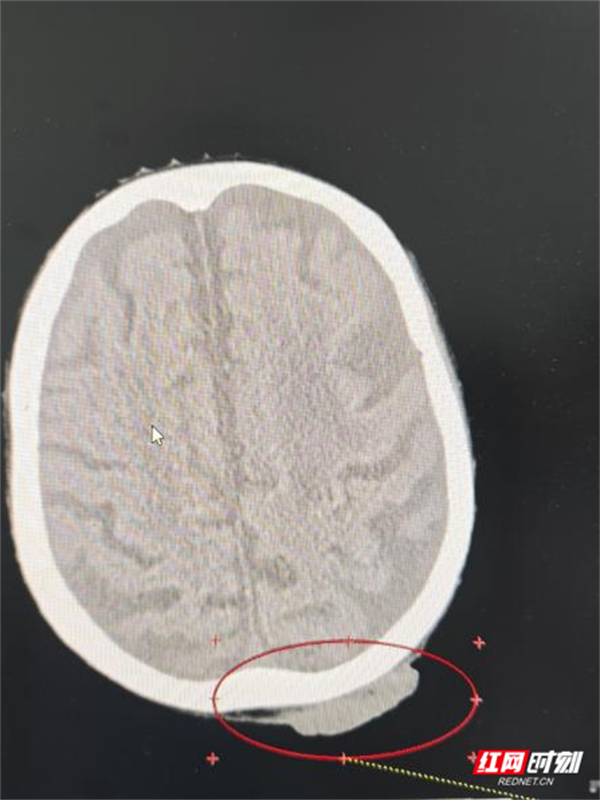

医生为谭奶奶进行了头部MRI等详细检查后,确诊她患“头皮恶性肿瘤鳞癌Ⅲ期”。这一结果让她和家人的心情跌落谷底——在他们看来,肿瘤本身就是难以治愈的疾病,更何况高龄老人还伴有多种基础疾病。

皮肤癌是常见的恶性肿瘤,病理类型以基底细胞癌和鳞状细胞癌为主。其中,鳞状细胞癌的恶性程度相对较高,生长更快,也更容易发生局部侵袭和淋巴结转移。虽然手术切除是首选且主要的根治方式,但在临床上面临诸多实际情况:例如肿瘤生长在鼻、眼、耳等面部关键部位,手术可能严重影响外观与功能;患者年事已高或合并多种基础疾病,无法耐受麻醉与手术;以及部分局部晚期病灶已失去最佳手术时机。

肿瘤血液科副主任黄华深知,对于这样的高龄患者,治疗不仅是技术活,更是“心术”。他与患者和家属充分沟通,用通俗易懂的语言介绍了现代放射治疗方案。这是一种通过三维精准定位技术,再利用高能射线精准靶向肿瘤区域,从而最大限度地保护周围正常组织,把握“控制肿瘤”与“保全生活质量”之间的平衡,这番话大大缓解了谭奶奶和家属原先对“化疗”等治疗的误解与恐惧。

肿瘤放射治疗团队为患者制定了详细、个体化的放疗治疗计划。经过40余的治疗,谭奶奶的疼痛日渐减轻,溃烂面逐渐缩小、愈合。更让她高兴的是整个治疗过程,没有出现呕吐和其他一些不良反应,食欲也没受太大影响,脸上也出现了往日的笑容。